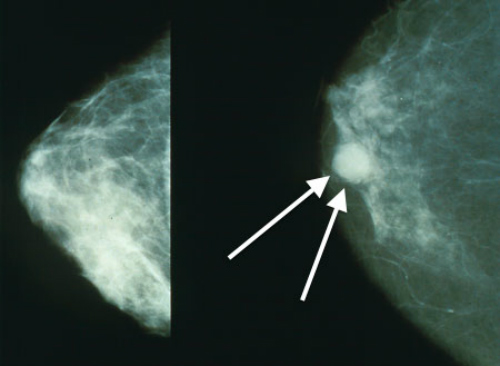

In fact, alcohol may increase all-cause mortality rates if cancer risk is factored. Previous meta-analyses have linked alcohol consumption with increased risk of a variety of cancers. (Figures 1 and 2.)